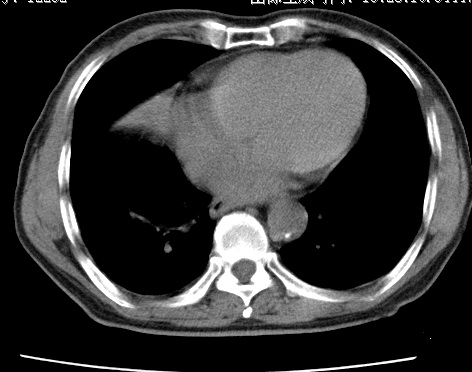

标题: CT24032:男65岁,咳嗽,吸烟20余年,无发热,咳痰 [打印本页]

标题: CT24032:男65岁,咳嗽,吸烟20余年,无发热,咳痰

考虑右肺中叶不张,请大家发表意见

右肺中叶不张、肺门轮廓增大,占位不除外;建议增强,必要时支气管镜详查。

右肺中叶支气管闭塞,中叶肺不张,右侧肺门见肿块影。中心型肺癌的可能大。建议支气管镜检查。

右中叶体积明显缩小,且其支气管未显示,先考虑:中心型肺癌班右中叶肺不张。

建议:支气管镜检查。

考虑右肺中叶中央型肺癌并右肺中叶肺不张;建议:行纤支镜检查。

右肺门旁类圆形肿块影,右肺中叶不张,建议纤支镜检查。

1右肺门旁类圆形肿块影,右肺中叶不张,建议纤支镜检查

2右侧胸膜增厚,右侧叶间胸膜区钙化

3右肺下叶小囊状透亮影考虑肺气肿